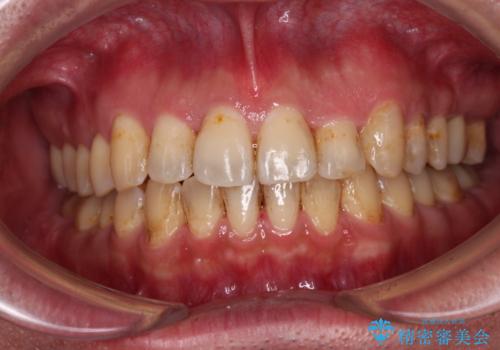

- ラミネートベニアにて着色歯を被覆していましたが、周辺の変色目立ったり、歯石が付きやすくなったりしたため、クラウンへの交換を希望された方です。

また、左右奥歯にも問題があるのでそちらの治療も希望されていました。

上下前歯 オールセラミック(ジルコニアクラウン)にて補綴

ラミネートベニアをクラウンへ変更したことで、歯の周辺の清掃性が向上され、更に審美面も大きく改善されたことで、患者様には大変満足していただけました。